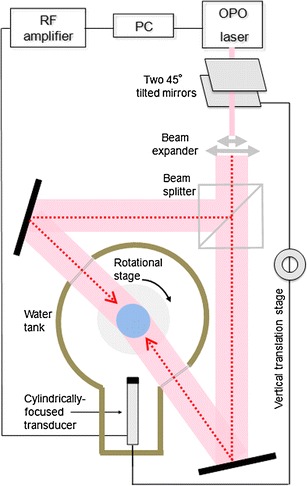

Optoacoustic Signal Acquisition

Multiwavelength MSOT experimental setup, shown in Fig. 1, was based on a tunable MOPO laser (Quanta-Ray MOPO-700; Spectra-Physics, Mountain View, CA, USA) pumped by a Q-switched Nd:YAG laser (Quanta-Ray Lab-Series 190–30; Spectra-Physics) operating at its third harmonic (355 nm). The pulse duration of the laser was less than 10 ns and the repetition rate is 30 Hz. The output laser beam size was adjusted to fit the size of the specimen. The 50/50 beam splitter (BSW16; Thorlabs) splits the beam into two equal-intensity parts being guided from two opposite directions onto the object’s surface through two transparent windows in the imaging tank filled with water. In this way, optimal excitation conditions close to uniform illumination were achieved. The estimated light fluence upon the surface of the specimen was 2 mJ/cm2, a level well below the permissible exposure limit [16] of 20 mJ/cm2 at the wavelength range used here for the imaging. A wideband piezoelectric PZT transducer (V319, 3.5 MHz central frequency, Panametrics-NDT UT Transducers, Olympus) was used to detect optoacoustic signals from the illuminated sample. The transducer was cylindrically focused in the imaging plane (38 mm focal distance) to allow 3D data acquisition via vertical scanning. Two 45° tilted mirrors were used to change the beam height by moving the bottom mirror with a vertical translation stage. The beam splitter and the ultrasonic transducer were translated by the same stage, thus both the illumination and detection planes were translated simultaneously to allow for 3D image acquisition via vertical scanning. The samples were mounted on a rotational stage so that in-plane tomographic data acquisition was done by 360° rotation of the sample. A 14-bit resolution PCI digitizer with a sampling rate of 100 MS/s (NI PCI-5122; National Instruments, Austin, TX, USA) was used to record the time-resolved acoustic signals detected by the transducer. We placed a photodiode (FDS010, 200–1100 nm, 1 ns Rise Time; Thorlabs) in the vicinity of the laser output window and recorded the intensity change of scattered light for each pulse in order to normalize the detected signals for laser output instabilities. In this way, quantitative readings of pulse-to-pulse laser intensity variations over broad wavelength range were obtained by calibrating the measurements using spectral response curve of the diode. This continuous power monitoring was of critical importance for multispectral reconstructions since some of important biomarkers may present only a small variation of the optical absorption over highly absorbing background, in which case even small quantification inaccuracies may lead to flawed results. The laser, stage controllers, and data acquisition were all synchronized via Labview-based interface (National Instruments). Single-wavelength two-dimensional data acquisition took approximately 30 s. Generation of a full 3D data set with, e.g., three wavelengths and ten vertical slices would take about 20 min. Image reconstruction for each vertical slice required 3 s and was performed by using a two-dimensional filtered back-projection (cylindrical Radon) algorithm [17].

Fig. 1.

Schematics of the multispectral optoacoustic tomography (MSOT) experimental setup.